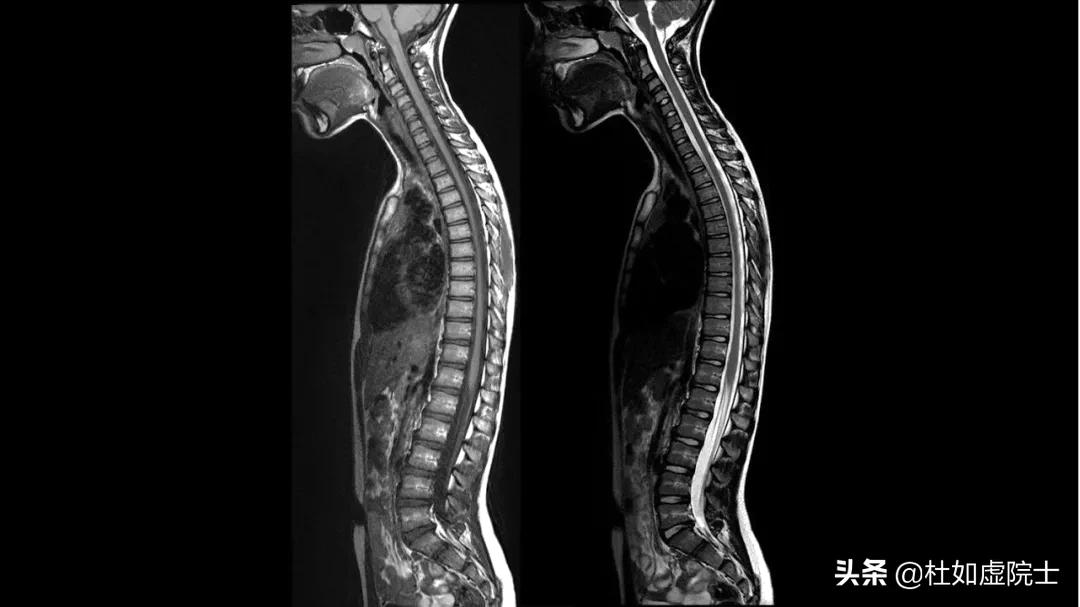

下表是核磁共振与 CT 两者特点的比较。图 14 展示的是一张核磁共振图像及相应的CT 图像。你能分辨出哪一张是核磁共振图像吗?

图 14,左边是核磁共振图像,右边是 CT 图像